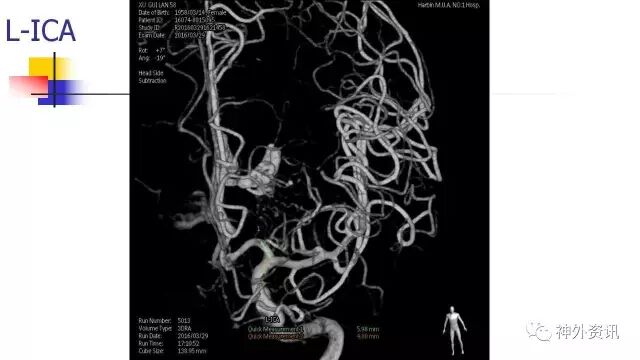

L-ICA正位动态